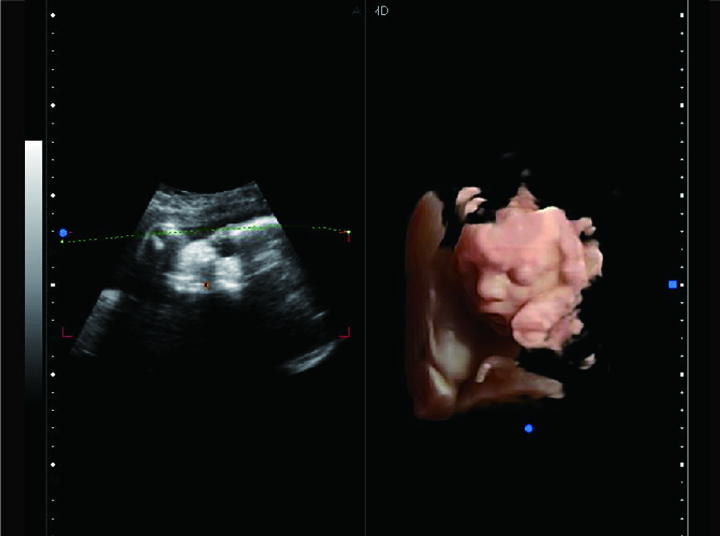

HD Virtual

HD Niche